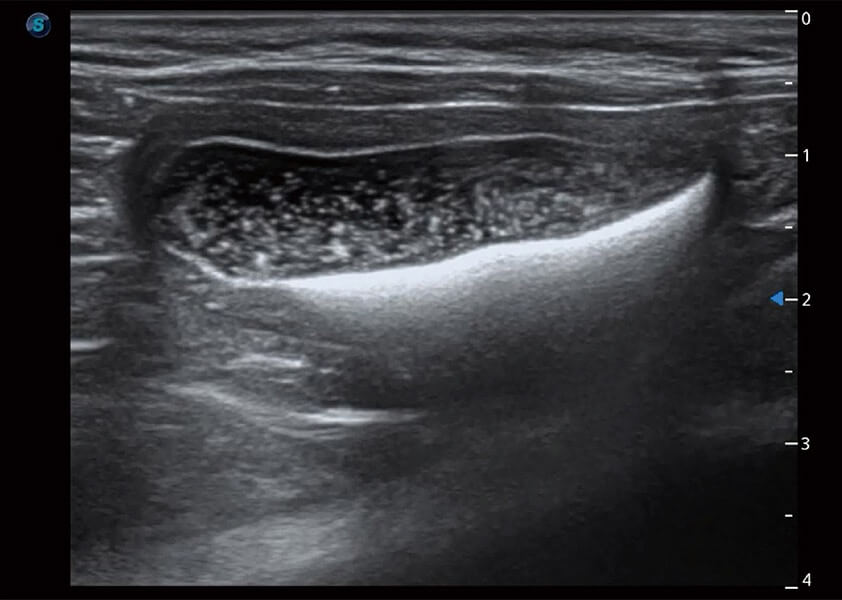

ProPet 60 作為一款高端臺(tái)式動(dòng)物超聲設(shè)備,為動(dòng)物醫(yī)生的日常診斷提供了一系列貼合動(dòng)物臨床需求、解決臨床實(shí)際問(wèn)題的高級(jí)成像功能。憑借全系列高清探頭,滿(mǎn)足醫(yī)生對(duì)腹部、心臟、生殖、淺表、肌骨等成像的所有需求,切實(shí)幫助您提升檢查效率,提高診斷信心。